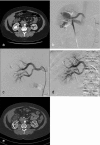

Arteriovenous malformations (AVMs) are high-flow vascular anomalies that have demonstrated a very high recurrence rate after endovascular treatment, surgical treatment, or a combination of both. Surgical treatments have shown good response when they are small and well localized but a poor response when diffuse. A better understanding of the nature of the lesion has led to a better response rate and a safer treatment for these patients. This has been accomplished through a detailed understanding of the angioarchitecture of the lesion, enabling a tailored approach in reaching and targeting the nidus of the AVM with different liquid embolic agents, more specifically ethanol. Flow reduction techniques help in exposing the nidus to sclerosant agents. A clinical classification, the Schobinger classification, will help determine the appropriate time to start or to pursue therapy.